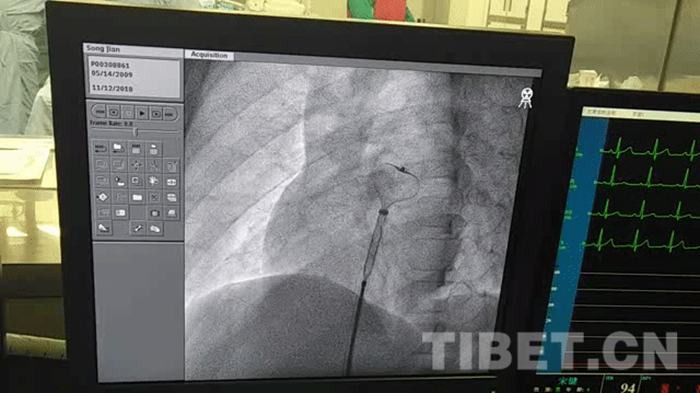

图为宋键进行心脏介入手术时,放入封堵伞。 摄影:孙健

北京电力医院名誉院长、心血管内科主任刘惠亮教授及心血管内科副主任张蛟医生负责此次心脏介入手术,麻醉科主任孙立智及超声科主任侯海军配合手术。几位医生一大早就来到病房,检查宋键的身体状况。据刘惠亮教授介绍,宋键的房间隔缺损属于中等缺损,平时可能不会出现危险状况,但是做用力动作时,会导致心脏的右房压力超过左房,右房形成的栓塞跑到左房,就会产生危险,所以选择介入手术是十分必要的。“宋键是个幸运的孩子,在‘同心•共铸中国心’项目的帮助下,可以来到北京接受治疗,这也体现了党和国家对民族地区孩子的关心。”